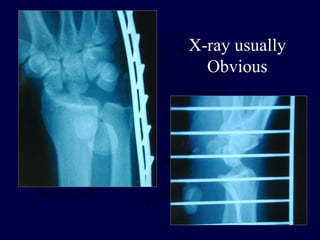

X-ray usually

Obvious